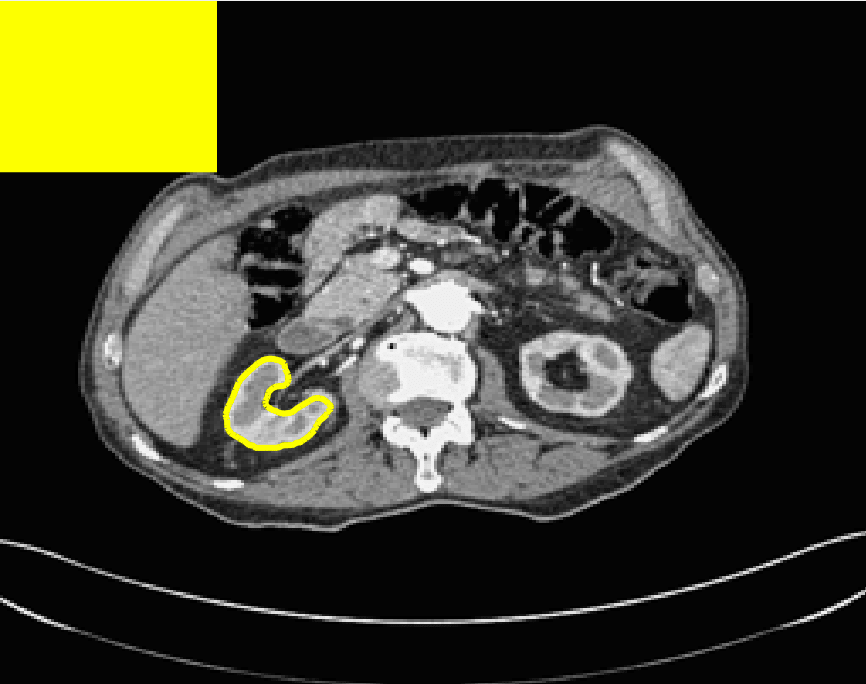

The motivation for this work comes from observing contradictions in using piecewise-constant intensity fitting terms in selective segmentation. Whilst good results are possible with this approach, the exceptional cases lead to severe limitations in practice. This is quite common in medical imaging as demonstrated in Fig. 1, where the target foreground has a low intensity. Given that the corresponding background includes large regions of low intensity, the optimal average intensities for this segmentation problem are and . For cases where , we see that by (1), almost everywhere in the domain . This means that it is very difficult to achieve an adequate result, without an over-reliance on the user input or parameter selection.

for and as defined in (33). This is consistent with respect to the intensities of the observed object and the concept of selective segmentation. In Fig. 3 we see the difference between CV and the proposed fitting terms for given user input on a CT image. For the CT image, the CV fitting terms are near 0 within the target region. This is despite there being a distinct homogeneous area with good contrast on the boundary. This illustrates the problem we are aiming to overcome. With the proposed fitting term this phenomenon should be avoided in cases like this. By defining as in (33) there is no contradiction if the foreground and background intensities of the target region are similar.